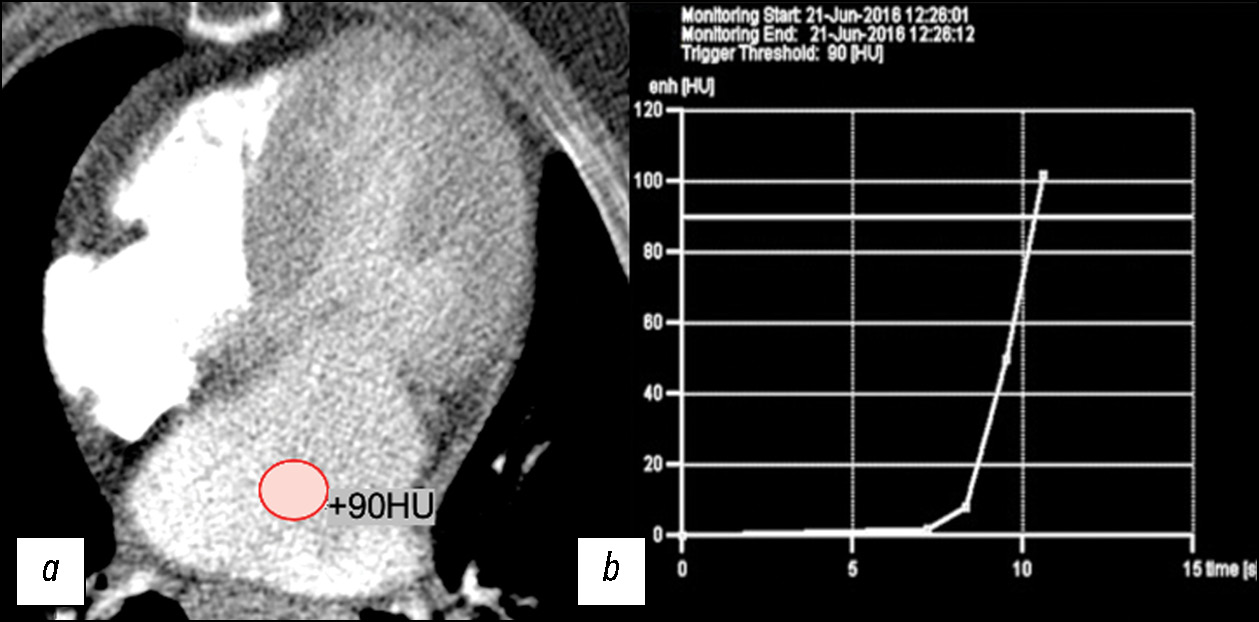

在肥厚型心肌病术前诊断中心脏计算机断层扫描的诊断能力

摘要

论证。借助各种诊断设备和最新扫描技术研究肥厚型心肌病的综合方法,将确保肥厚型心肌病患者的高质量控制和有效治疗。为了研究左心室重构的表型变异,并与二尖瓣的腱索乳头肌和心肌结构的异常相结合,在新一代扫描仪上引入创新的技术和计算机的计算,具有现实意义和前景。

目的 — 研究在肥厚型心肌病表型术前诊断中计算机断层扫描的能力。

材料和方法。对47名肥厚型心肌病患者(平均年龄为52±7周岁)的术前矫正数据进行回顾性分析。为了研究心房、冠状动脉的异常和二尖瓣的形态,我们采用了自己开发的规程和阈值为90HU双相注射造影剂,自动监测左心房腔内的造影剂团。为了研究心肌的结构变化,利用构建延迟对比碘图对双能量计算机断层扫描获得的数据进行分析。所有肥厚型心肌病患者都被分为不同的形态学类型。 对每个病例的脉络-乳头器的解剖结构进行了评估。

结果。我们的研究表明肥厚型心肌病表型体现的易变性,通常可分为5种形态类型,但并不局限于这些变体。26名患者(55%)具有肥厚型心肌病的弥漫性隔膜形态表型。 5名患者(11%)发现室间隔表型,其中2名患者 (4%)的室间隔表型伴有左心室心尖部隆起/动脉瘤。 8名患者(18%)发现局灶性基底表型,4名患者(8%)发现同心表型,另有4名患者(8%)发现了心尖部表型。大多数患者被诊断为二尖瓣腱索乳头肌异常,分为乳头肌数量和位置异常,以及腱索与肌肉比例异常。10名患者(21%)的冠状动脉心内走行,其中3 名患者(14%)发现动态狭窄迹象。所有患者在延迟对比图上都显示出局灶性碘沉积。13名患者中10名(76%)的ECV细胞外体积分数值超过正常范围。双能量计算机断层扫描显示的平均左心室心肌ECV为30.58%(95%置信区间为27-34%)。

结论。我们在各代计算机断层扫描仪上开发的扫描规程,使其能够在一项研究中确定肥厚性心肌病形态类型的特征模式,并详细解释心脏的心室和瓣膜系统的几何形状、左心室的功能和冠状动脉床的状态,以及左心室心肌的结构变化。